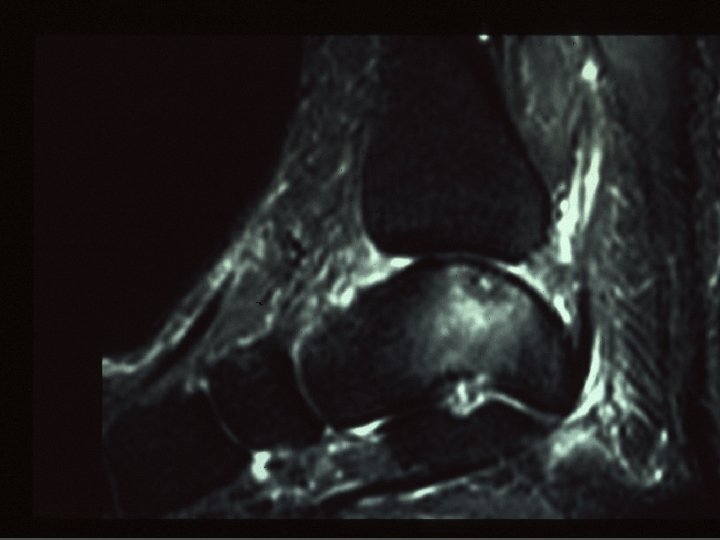

SCP microtraumatique : Lésions n n n Inflammation récessus capsulo-ligamentaires postérieurs Arthrose talo-crurale ou sous-talienne postérieure # de stress tibio-talienne postérieure Lésion ostéo-chondrale dôme talien postérieur Tendinopathie Fléchisseur Propre de l’Hallux (TS > fissures IT)

SCP : Diagnostic = Clinique Mais le diagnostic « lésionnel » = imagerie But : Préciser : - anatomie - définir lésion n Moyens : - RX - Echo (tendon FPH) - CT , arthro. CT, IRM , scinti n (surtout si trauma pour exclure # méconnue)

SCP : Diagnostics différentiels Avec flexion plantaire douloureuse - Tendinopathies du Long Fléchisseur de l’Hallux . Situation : gouttière du processus post. Du talus ( tunnel ostéo-fibreux non extensible) . Facteur favorisant : jonction MT basse - jonction N = niv. Art. tibio-talienne - jonction basse = niv. Talus ou face médiale calca. n (néanmoins anomalies le plus svt asymptomatiques) - Lésion ostéochondrale dôme talus ou du pilon tibial (séq. T , kyste , …)